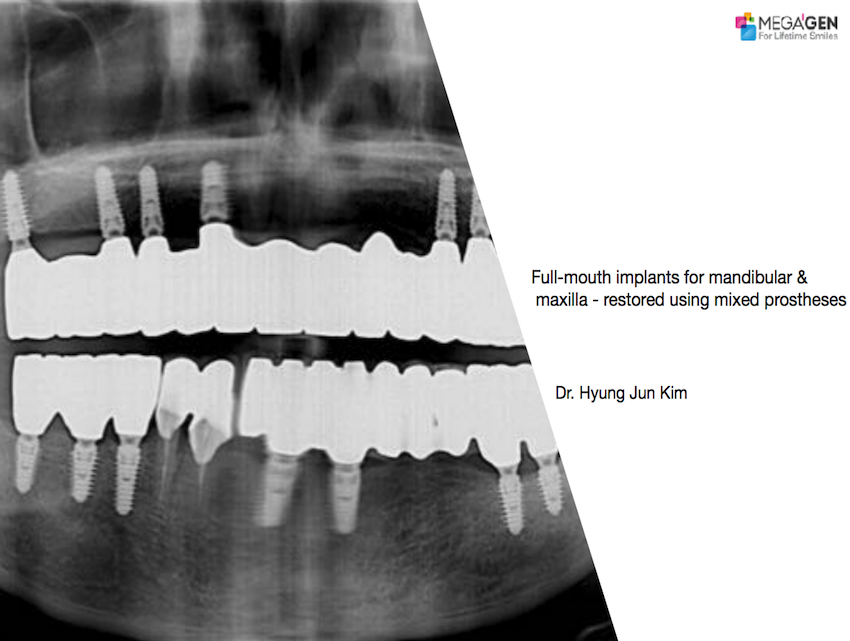

Full-mouth implants for mandibular & maxilla – restored using mixed prostheses

Dr. Hyung Jun Kim,Edentulous,Maxillary Anterior,Maxillary Posterior,Mandibular Anterior,Mandibular Posterior,#12,#22,#32,#45,#14,#24,#36,#46,#15,#25,#37,#47,#17,#27,#41,Immediate Placement,AnyRidge,Full-mouth implants,Full mouth rehabilitation,Octa abutment,Long-term clinical case,Biological stability